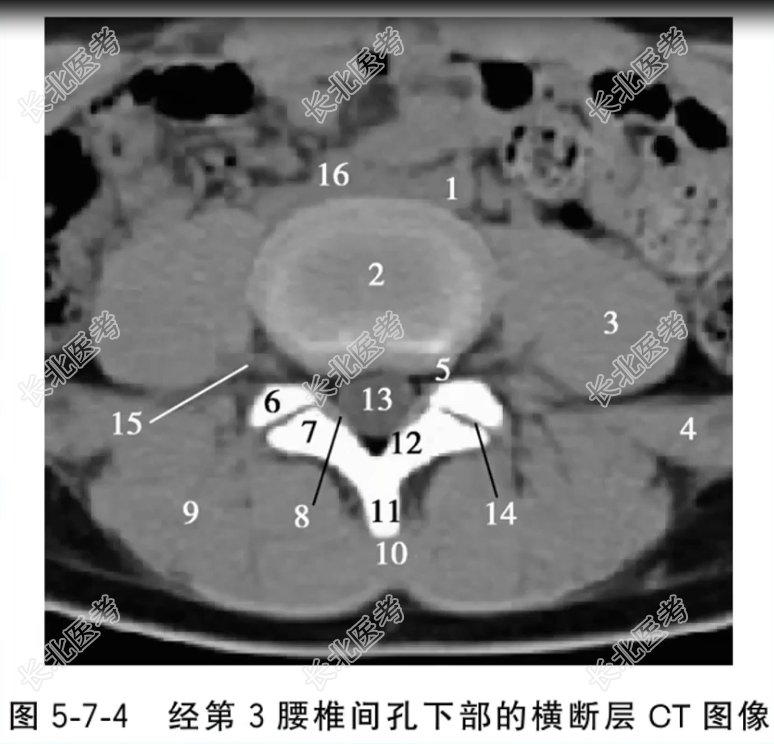

- 单项选择题经第3腰椎间孔下部的横断层CT图像中,标记为2、5、13的结构分别是

A、第3腰椎间盘、第3腰椎间孔、硬脊膜囊

B、第3腰椎间孔、第3腰椎间盘、硬脊膜囊

C、硬脊膜囊、第3腰椎间孔、第3腰椎间盘

D、第3腰椎间盘、硬脊膜囊、第3腰椎间孔

E、第3腰椎间孔、硬脊膜囊、第3腰椎间盘